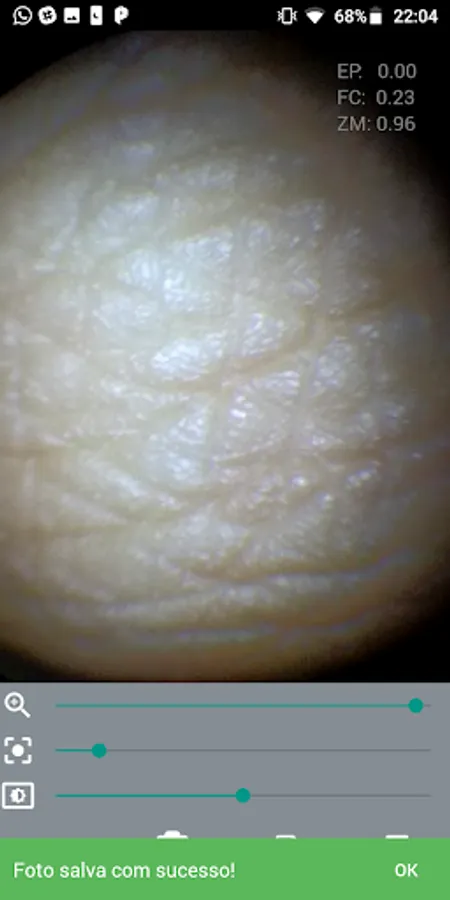

The M-Scope Mobile Endoscope is an application to be used in conjunction with the M-Scope kit, an endoscope coupling adapter + portable led light source, which can be used to attach a smartphone to an endoscope, to aid capture and sharing gallery of exams:

Nasofibrolaryngoscopy

Otoscopy

Hysteroscopy

Arthroscopy

Bronchoscopy

And other video-endoscopy exams and procedures in general.